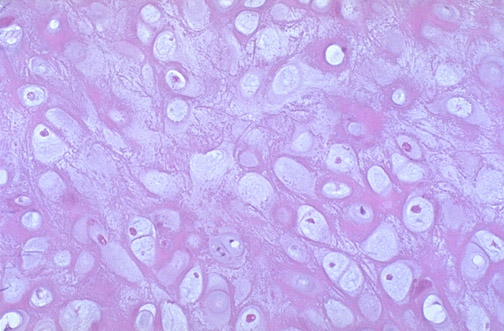

| The normal epiglottis has a firm but movable shape based upon the presence of elastic cartilage below the submucosa. Elastic cartilage (also found in the nose and the external ear) has prominent pink-staining elastic fibers between the cartilagenous nuclei. On one side is respiratory epithelium. When swallowing, the epiglottis closes over the respiratory tract above the larynx, and the swallowed food or fluid passes over the squamous epithelial-lined side of the epiglottis into the esophagus. |